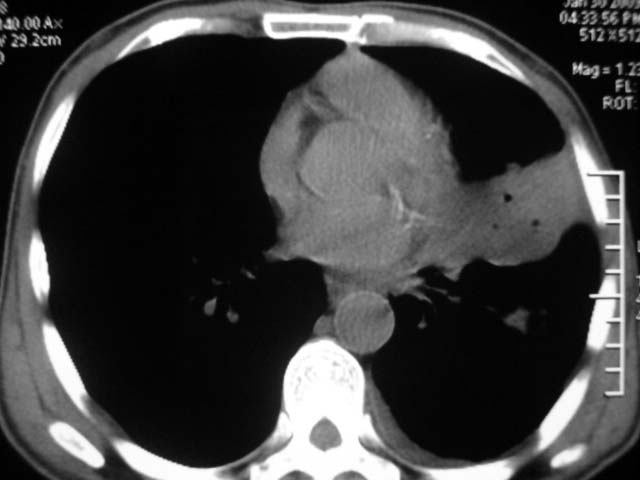

男,52岁,发热2月,糖尿病史。

抗结核治疗irpz方案,血糖未治疗,空腹15.9左右。症状无好转,左胸痛。

复查ct

2、双肺见多发片状及结节状高密度影,大多数病灶中心均见“空泡征”。

3、纵隔内淋巴结肿大。

结果:两肺继发性肺结核并曲霉菌感染。